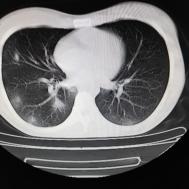

性别:女,年龄:26岁,低热,轻微胸痛,支原体阳性

[影像描述]

两肺内及胸膜下多发斑片状高密度影,部分病灶密度较淡,部分实变,边缘可见渗出改变。